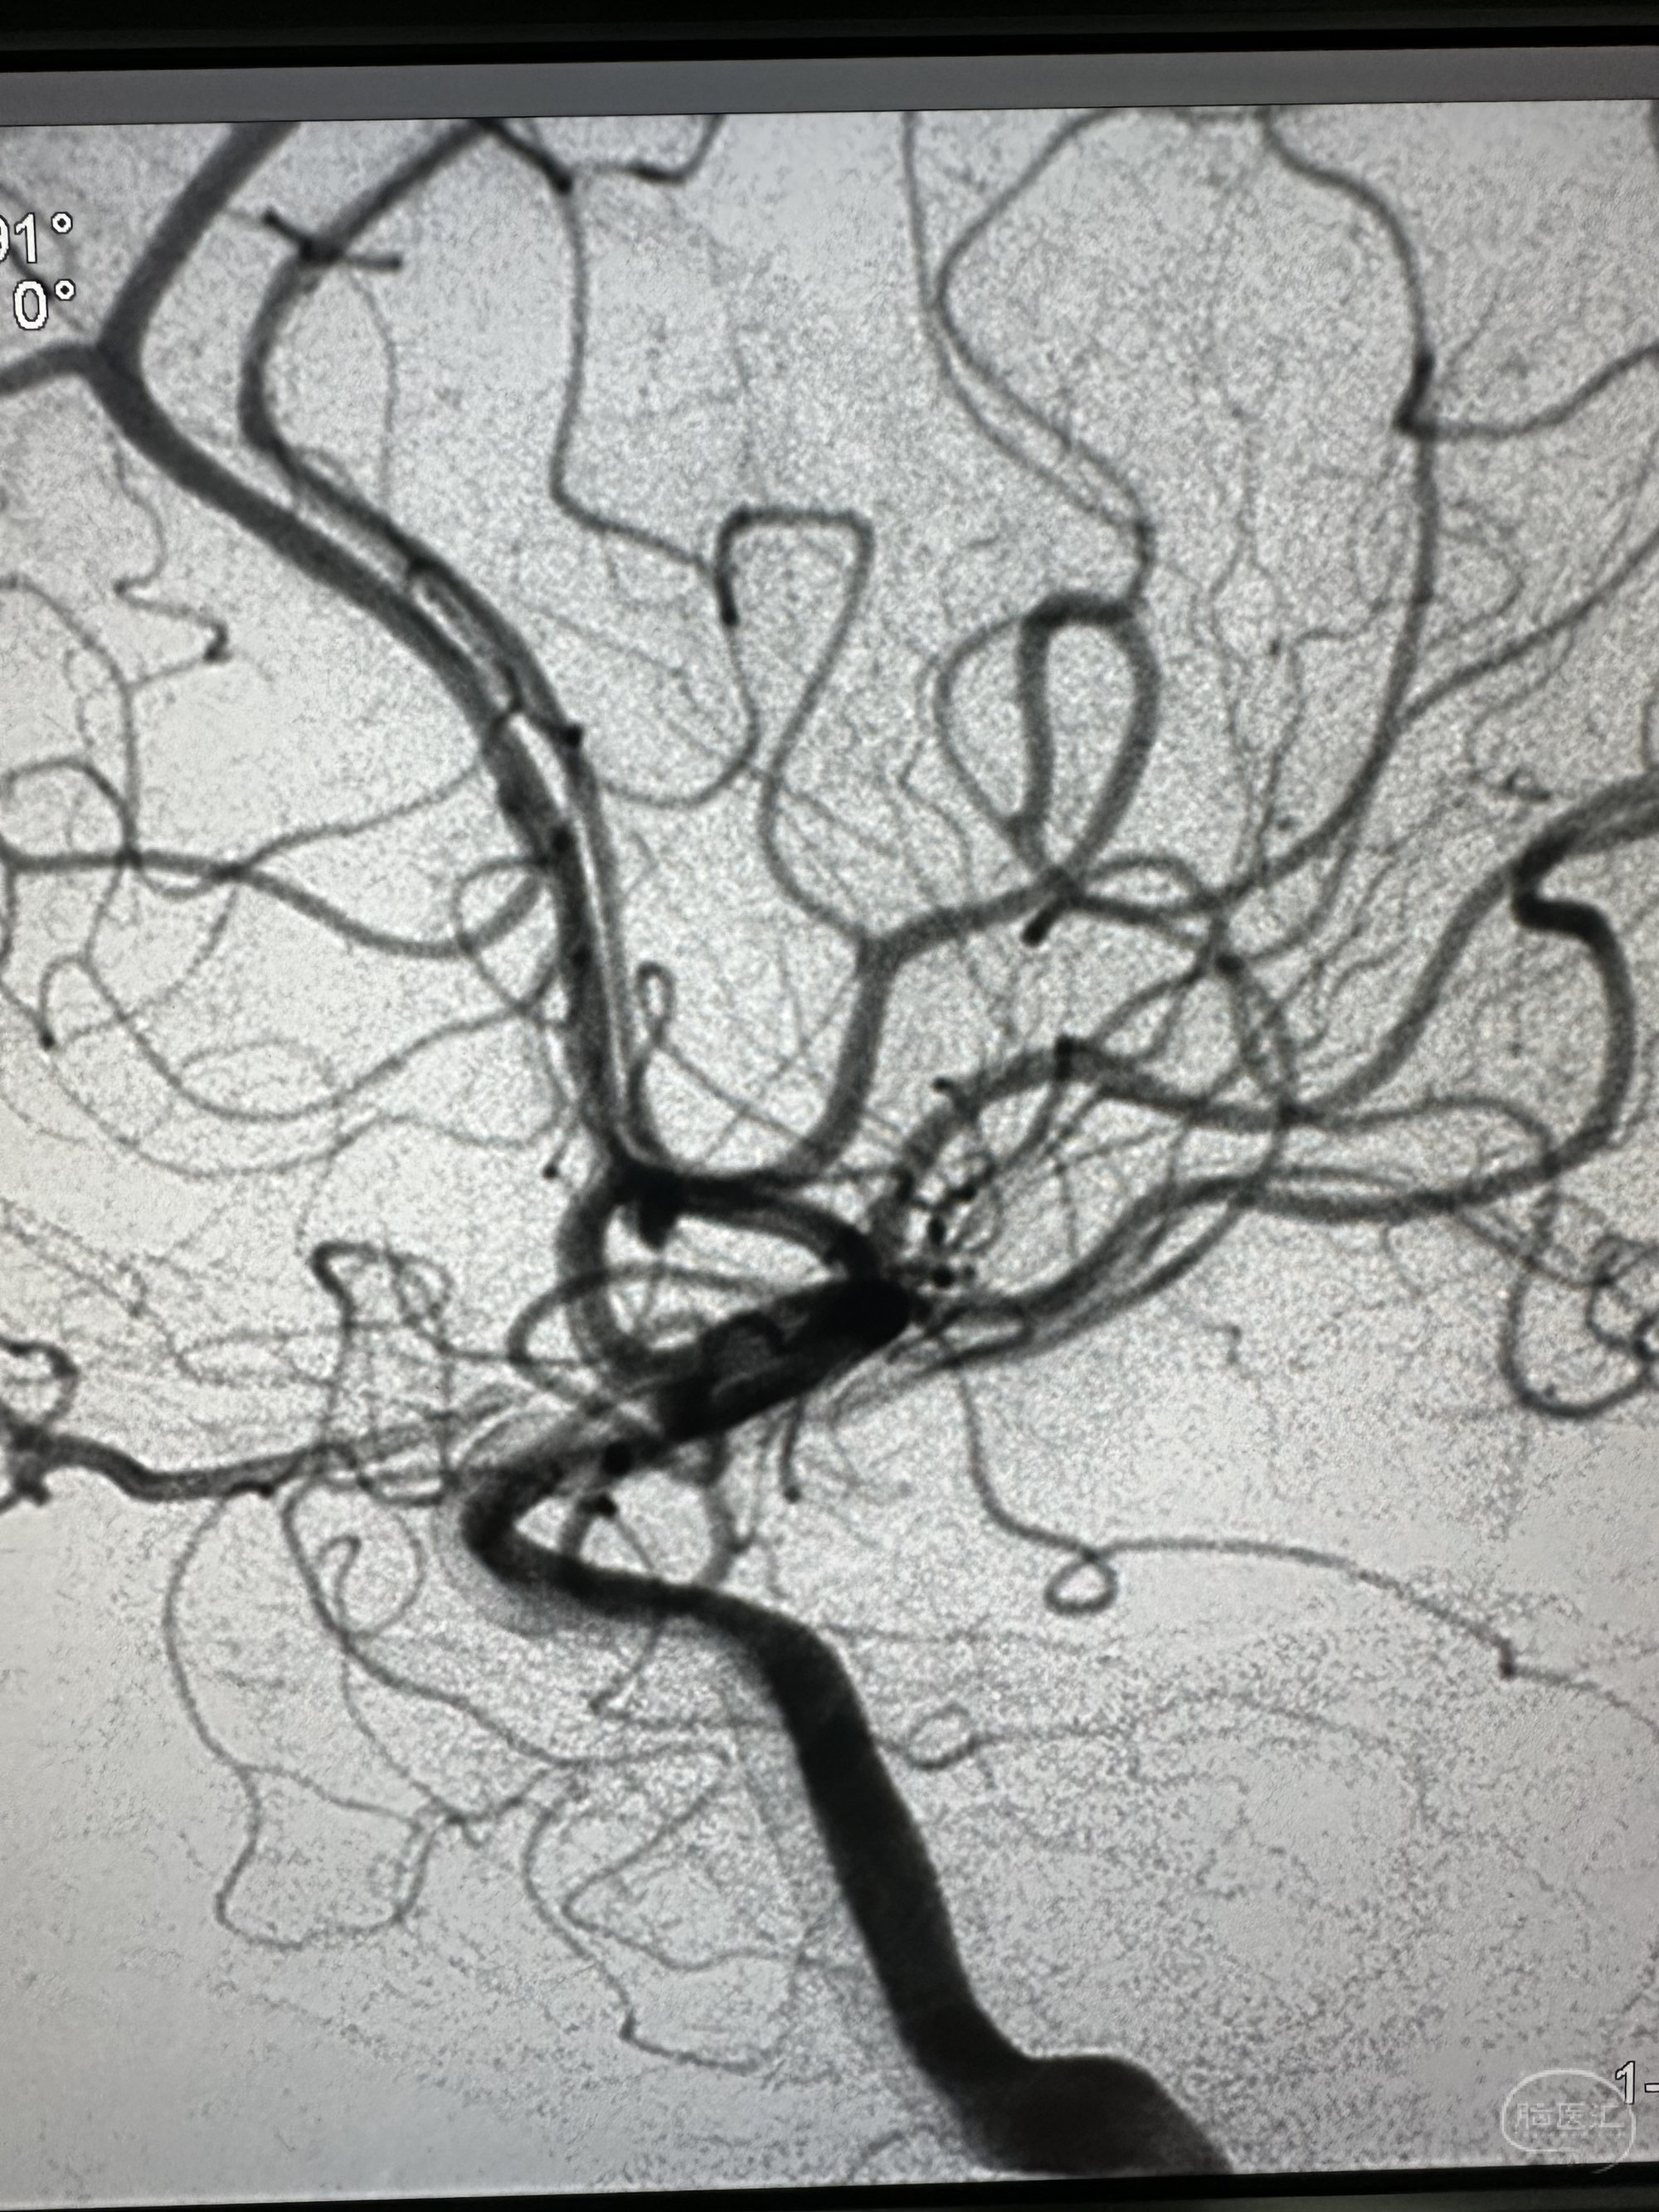

对侧造影